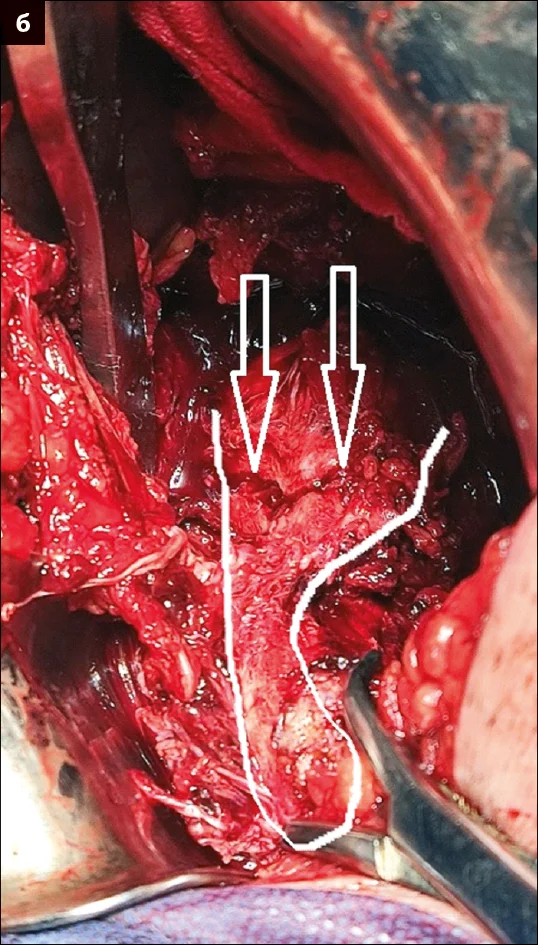

– У даного пацієнта під час планування оперативного втручання спостерігалася масивна гематома та набряк ділянки таза. Після проведення доступу й ревізії лівої половини таза та лобкової кістки справа було виявлено ушкодження анастомозуючих судин corona mortis (анастомоз між затульними та нижніми епігастральними судинами) і триваюча кровотеча в ділянці for. оbturatoria. Для ліквідації ушкодження було виконано взяття на затискачі Більрота анастомозуючих судин corona mortis із наступним їх перев’язуванням (рис. 6).

Рис. 6. Зображення ушкодження судин: а – вскриття внутрішньо-тазової гематоми; б – взяття на затискачі Більрота анастомозуючих судин corona mortis із наступним їх перев’язуванням;

в – інтраопераційна візуалізація

for. оbturatoria з венозною кровотечею у цій зоні; г – схематичне зображення ушкодження анастомозуючих судин

corona mortis